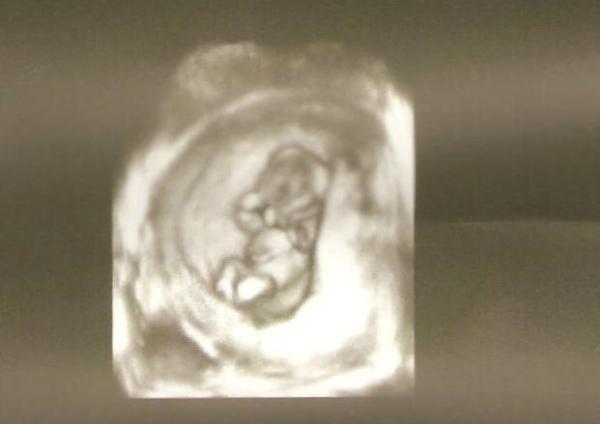

Dodane przez: Misiaczek Opis zdjęcia: 3.5 miesiaca;) maluiszek Podziel się ze znajomymi! Skopiuj i prześlij poniższy link: URL: |